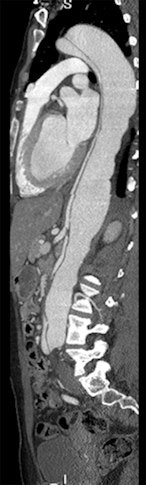

Images of the whole aorta were acquired using a wide-volume protocol; each volume was scanned in a single heartbeat with 16-cm anatomic coverage. The second volume was positioned to cover the whole heart to ensure that all the segments of coronary arteries were in the same dataset. The table is stationary during each acquisition, and then moves to the next location for the next CT data acquisition. Patient is a 23-year-old woman with Marfan syndrome combined with coronary-pulmonary fistula, and a Stanford type A aortic dissection. All images courtesy of Dr. Yu Li.

CTA of the aorta is a common imaging technique due to its speed and resolution, according to the researchers. But motion in the ascending aorta can be a problem without ECG gating. Using 320-detector-row CT, image quality is acceptable throughout, and for Stanford type A aortic dissection, CTA showed the relationship between the intimal flap, and the aortic valve and the coronary ostium "without obvious motion artifacts," they stated.